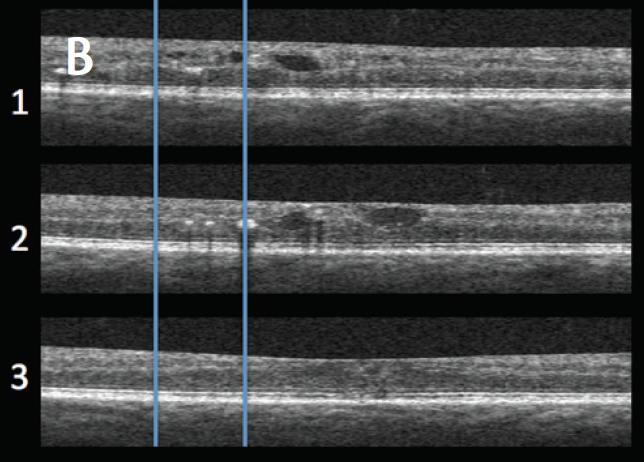

Figure 2. OCTA of a 77-year-old patient with DME. Pseudocolored, depth-encoded OCTA (red = superficial, green = deep, yellow = overlay) image shows mild capillary loss and foveal avascular zone (FAZ) abnormalities in the superotemporal quadrant (A). An area of green-colored reflectivity, delimited by vertical blue lines (A1, A2 A3), does not correlate with the bulk of hyporeflective intraretinal fluid spaces shown on OCT B-scans (B). These regions of hyperreflectivity have been noted in patients with DR and in patients with RVOs and do not correlate with the region of staining on late FA (C). We hypothesize that these areas correspond to regions of particulate debris (eg, hard exudate) with Brownian motion that is detected with OCTA. OCTA images obtained with AngioPlex. FA obtained with Spectralis (Heidelberg Engineering).

Our group has also shown that OCTA can demonstrate novel pathologic features that do not correlate with features on FA or OCT.6,8 For example, certain types of intraretinal edema are detected very well on OCTA, but these regions do not correlate with typical intraretinal fluid pockets on OCT or with late staining regions on FA (Figure 2).6,8 This finding has been demonstrated by our group in patients with DR6 and in patients with RVO.8 We have postulated that this finding occurs because even trace amounts of particulate debris (lipid and extracellular protein deposits such as hard exudates) within retinal tissue can generate OCTA signal from Brownian motion. The clinical significance of this finding is not yet clear, but it is the subject of ongoing investigation (unpublished data).